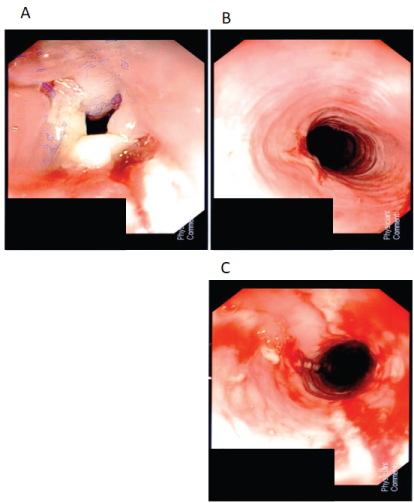

A 25-year-old woman diagnosed with Crohn's disease in 2000 presented with weight loss, nausea, vomiting, diarrhea, oral ulcers, and sitophobia. At the time of initial endoscopy she was found to have disease affecting her colon with deep ulcers extending from the sigmoid colon to the hepatic flexure as well as ulcers in her terminal ileum. She also had esophageal ulcers but no luminal narrowing (L3/L4 disease as per the Montreal Classification). She was initially started on oral prednisone but there was no improvement and she developed mania and suicidal ideation consistent with steroid psychosis. She also had no response to budesonide or acid suppression. From 2001 to 2003 she was on infliximab and methotrexate. Infliximab was discontinued because of anti-histone positive drug induced lupus. She was switched to adalimumab from 2006 to 2008 but this had to be stopped due to ongoing arthritis. From 2008 to 2010 she was treated with ustekinumab and methotrexate but continued to have evidence of both clinical and endoscopically active disease. In 2010 she received a temporary diversion ileostomy and in 2012 she went on to have a total proctocolectomy with end-ileostomy due to clinical improvement with the temporary stoma. Following the surgery she was maintained in clinical remission on topical fluocinonide 0.05% gel, azathioprine 100 mg daily, golimumab 200 mg every two weeks and esomeprazole 40 mg daily. She returned in 2013 with new onset dysphagia, significant weight loss and diffuse arthritis. Prior to this she had no esophageal symptoms. EGD was performed in August 2013 which showed severe ulceration and stricturing of the mid-esophagus requiring dilatation using a 30, 32 and 34 mm Bougie dilators (Figure 1A, Figure 1B and Figure 1C). She had repeat dilatation 1 month later. Biopsies from these procedures revealed acute and active chronic inflammatory infiltrate with no granulomas, inclusion bodies or evidence of malignancy. Given the isolated nature of the pathology in the mid-esophagus while on acid suppression therapy and lack of features consistent with other conditions, the esophagitis and stricture was thought to be consistent with foregut CD. At this time golimumab levels were measured using an assay designed for infliximab measurements and the result was 15.6 µg/ml (Prometheus Laboratories).

Figure 1: A) Esophageal ulceration and stricture pre-dilatation; B) Esophagus distal to the stricture; C) Esophageal stricture post-dilatation. View Figure 1